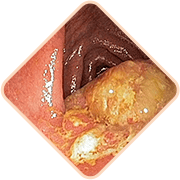

Gemorroy to'g'ri ichakning jiddiy

kasalliklarini yashirishi mumkin:

- Jarohatlar

- Ichakdagi qon ketishlar

- Nekrotik o'zgarishlar

- Saraton